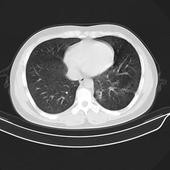

1.叶内型 较常见,约占75%。多位于左肺下叶后基底段,脊柱旁部位,其次为右肺下叶基底段部位,上叶部位较少发生。隔离肺组织呈不同程度囊性或实变,与周围正常气管支气管树缺少交通。镜检可见肺组织有单核细胞和巨噬细胞浸润和纤维化,支气管呈囊性扩张。若隔离肺组织与正常肺组织相交通,则可见管腔内脓性分泌物潴留,相应肺组织炎症细胞浸润,如中性多核细胞等。隔离肺组织血管通常为发育良好的弹性动脉,血管扭曲,管壁增厚,且肺动脉、肺静脉和体循环血管可形成毛细血管前吻合。

2.叶外型 较少见,约占25%。多位于左肺下叶后基底段,亦可位于纵隔内或肠下。隔离肺组织由胸膜包裹而与正常肺组织完全分离,切面呈褐色海绵状,镜检可见肺组织发育不全,甚至呈囊肿状。隔离肺组织的支气管与正常支气管无交通,故肺组织炎症少见。支气管多有不同程度扭曲和扩张。隔离肺组织血液供应主要来源于腹主动脉或其分支,而通过下腔静脉、奇静脉或半奇静脉引流,形成左-右分流。但亦有血液通过肺动脉供应和肺静脉引流者。